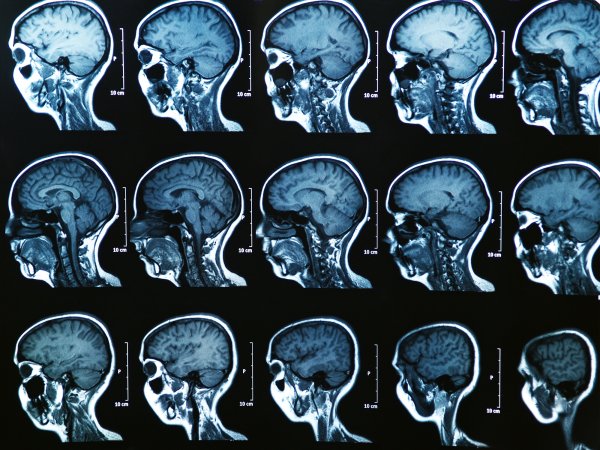

Football is one of the most popular sports in America. But recently it’s come under fire from coaches, parents, and medical professionals alike for the contact sports’ tendency to result in concussions—not just in professional football, but in college and youth leagues as well. There’s mounting evidence that repeated concussions can lead to a condition called chronic traumatic encephalopathy (CTE). The degenerative disease can cause severe neurological problems including memory loss, confusion, aggression, and dementia.

A helmet-less head has its own protective mechanisms. Cerebral spinal fluid surrounds each delicately squishy brain, and this liquid layer is often enough to protect the organ from various bumps. But a concussion occurs when the brain is accelerating extremely fast and then comes to a hard stop. At that point, the rapid change in momentum causes the brain to jostle inside the skull so much that the cerebrospinal fluid can’t protect it.